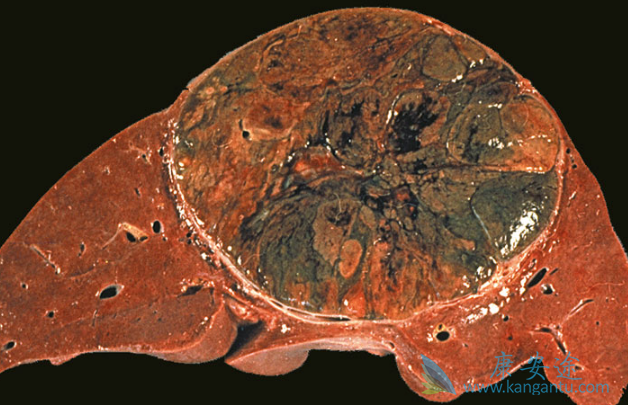

碧康仿制的乐伐替尼(Lenvima)一线治疗晚期肝癌,在总生存期方面非劣效于索拉非尼,在无进展生存期与客观缓解率显着优于索拉非尼。碧康仿制的乐伐替尼包装由卫材的20粒变为30粒,还是4毫克和10毫克两个规格。国内的患者可以亲自前往印度购买,或者通过像康安途这样的正规海外医疗机构协助购买。